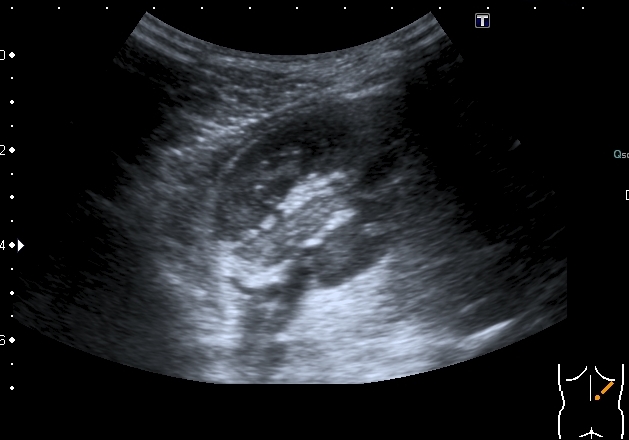

Левая почка

Она же

Поперечный скан